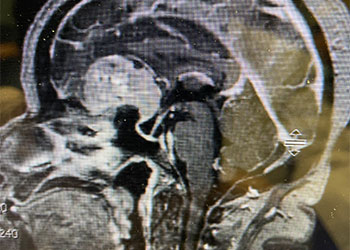

Figure 1: Sagittal post-contrast MRI. Figure 2: Axial post-contrast MRI. Postoperative images looked good (Figure 3). The patient felt better after surgery. His headaches were much […]